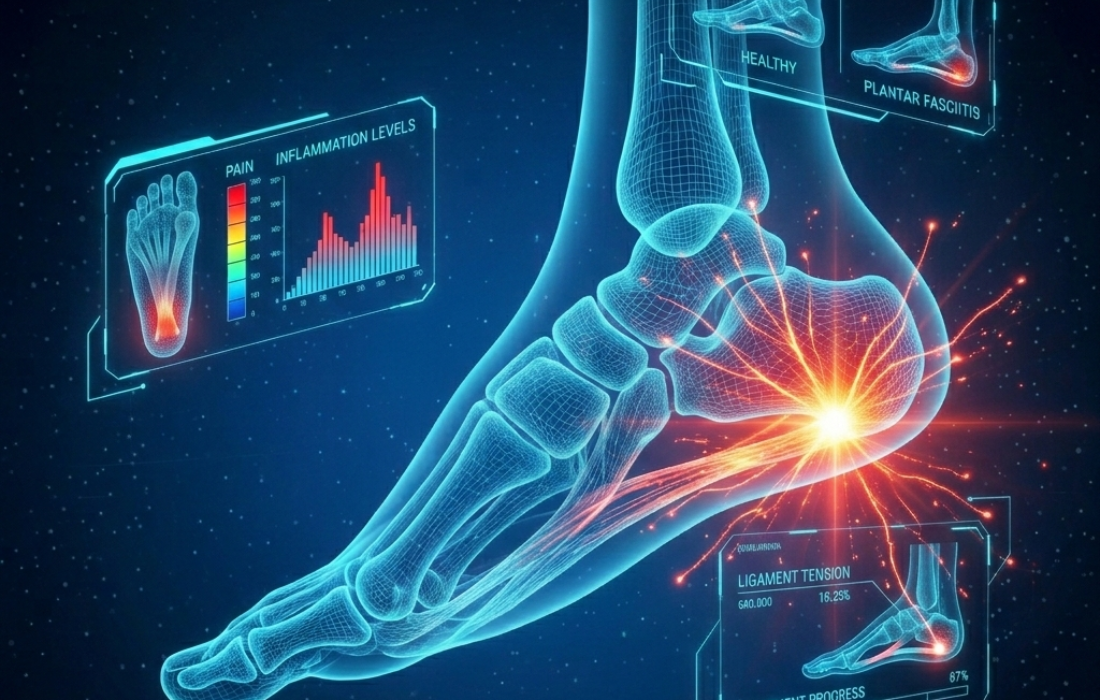

FASCITIS PLANTAR: POR QUÉ DUELE MÁS AL DAR LOS PRIMEROS PASOS DEL DÍA

En nuestro consultorio, observamos a menudo pacientes que acuden preocupados por un dolor en el talón que surge justo al levantarse por la mañana.